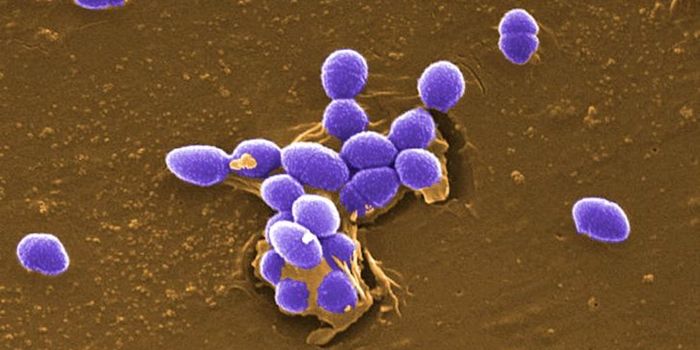

SEP 17, 2021Cell & Molecular BiologyMRSA (methicillin-resistant Staphylococcus aureus) is a well known superbug, a pathogenic microbe that can cause serious ...